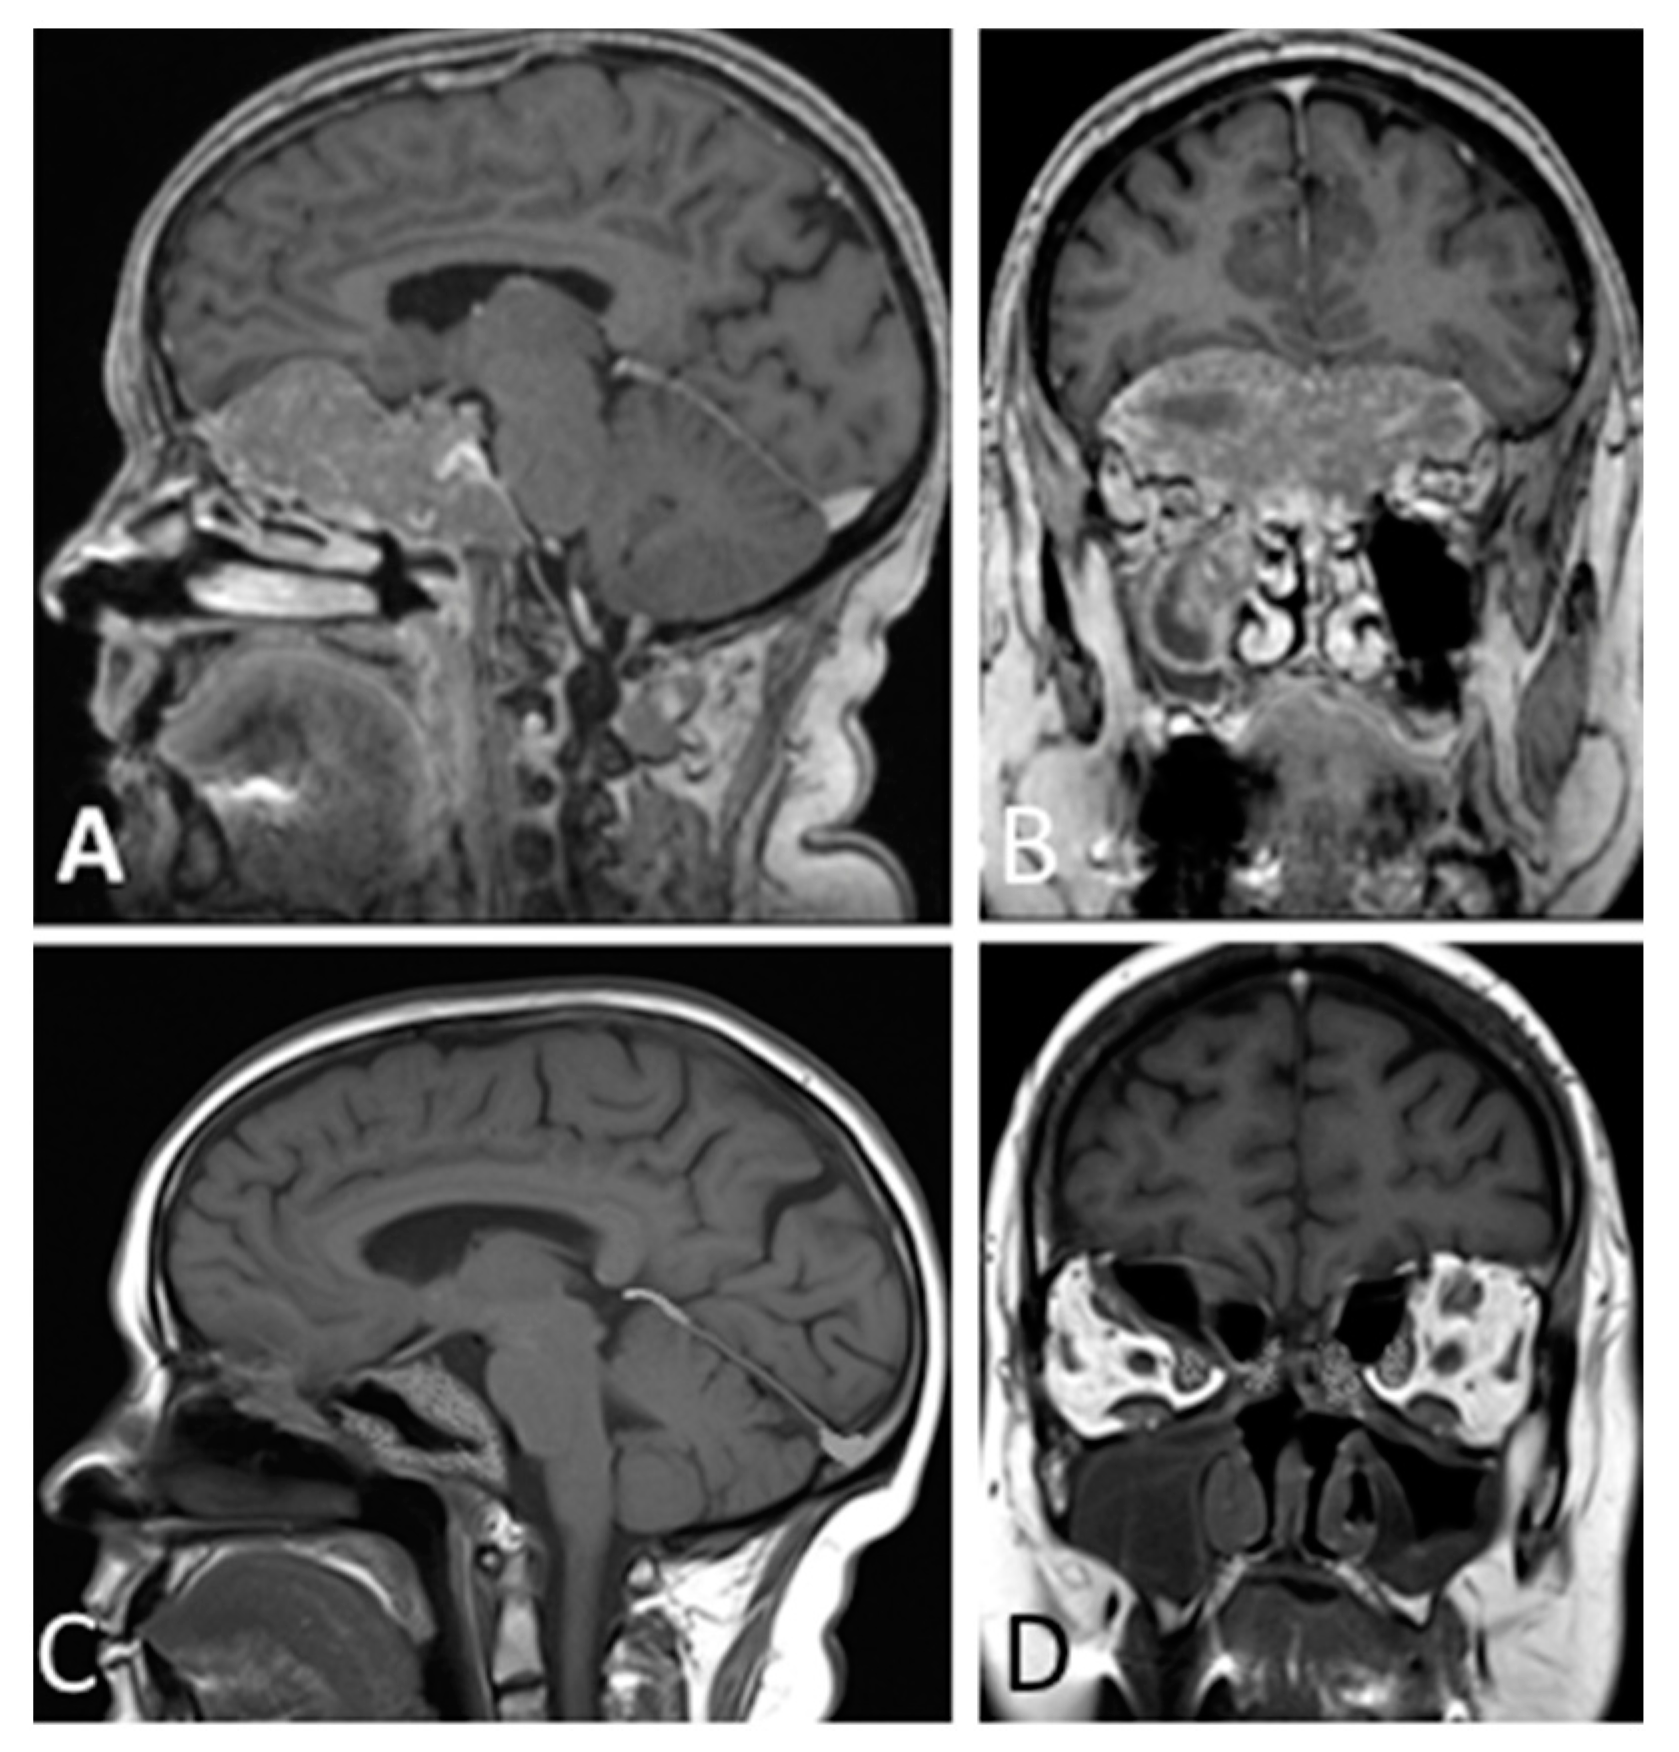

- Chibbaro, S.; Ganau, M.; Gubian, A.; Scibilia, A.; Todeschi, J.; Riehm, S.; Moliere, S.; DeBry, C.; Goichot, B.; Proust, F.; et al. The Role of Endoscopic Endonasal Approach in the Multimodal Management of Giant Pituitary Adenoma: Case Report and Literature Review. Asian J. Neurosurg. 2018, 13, 888–892. [Google Scholar]